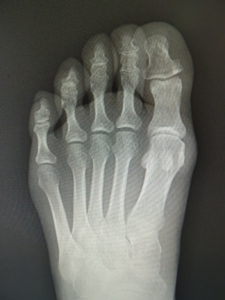

(図5)

手術前 手術後4年

(図6)

手術前 手術後

(図7)

真田理事長による手術の様子。外反母趾|症例 (左から 手術前、手術後、ワイヤ抜去後)